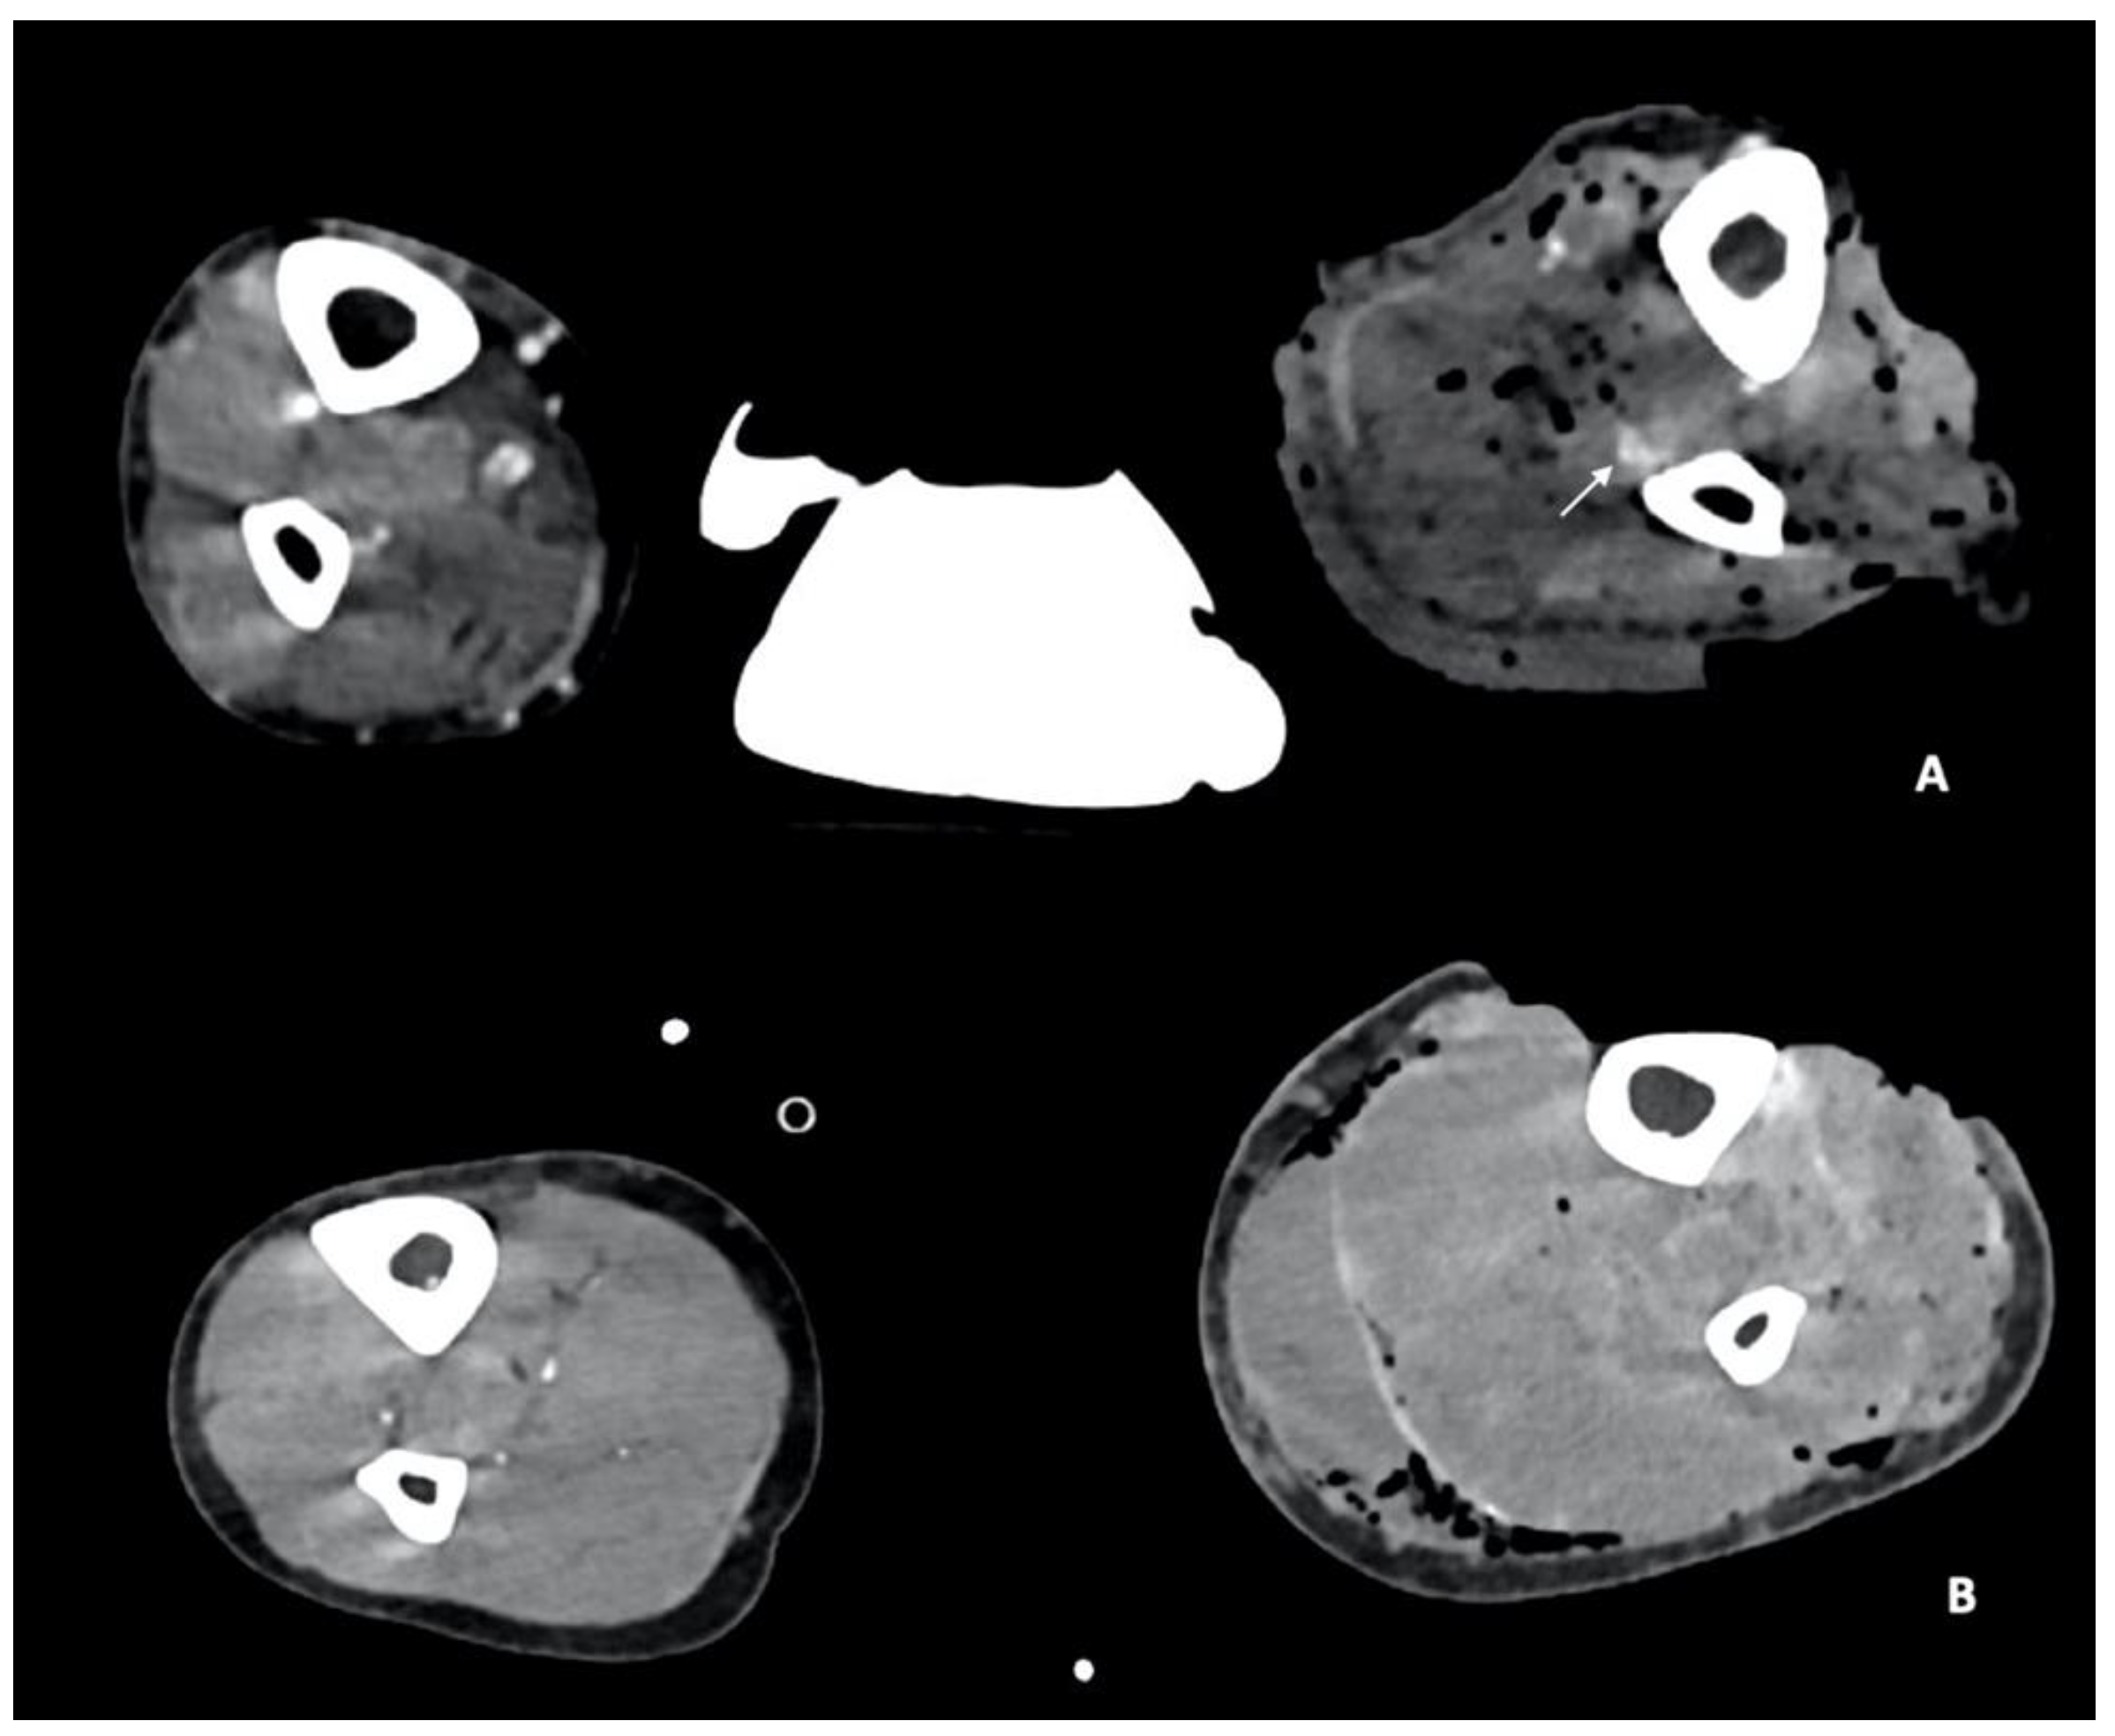

3.2. CTA Imaging Findings